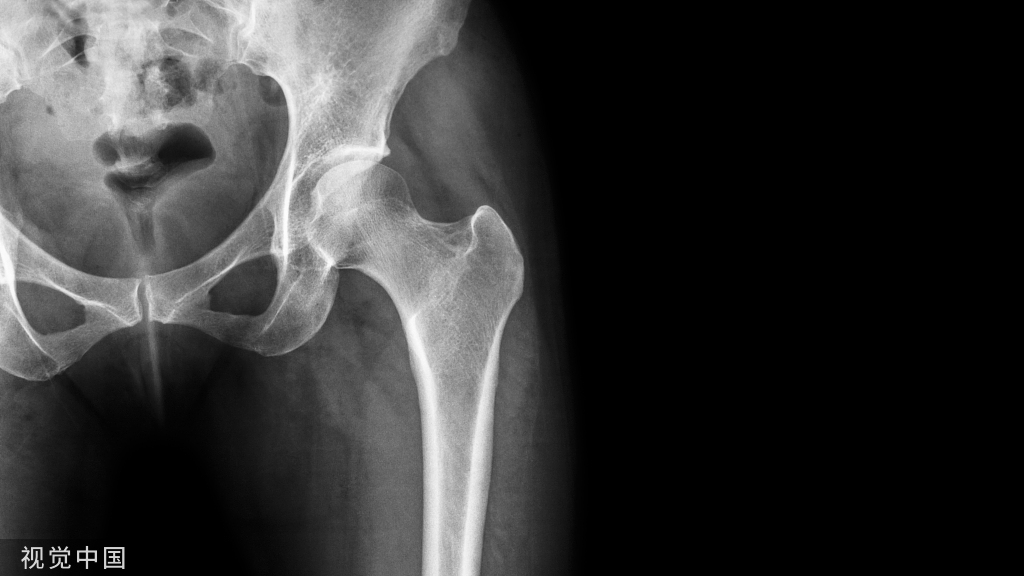

膝关节穿刺术常用于检查关节腔内积液的性质,或抽液后向关节腔内注药。膝关节腔内积液,需行关节穿刺抽液检查或引流,或注射药物进行治疗。关节腔内注射空气或造影剂,行关节造影术,以了解关节软骨或骨端的变化。

膝关节腔积液的原因:

1、受伤(与运动有关)膝关节扭伤、半月板损伤、侧副韧带或交叉韧带损伤。2、感染(结核)。3、类风湿性关节炎、滑膜炎。

当关节退变、运动过力或创伤,使得关节腔内乳酸、组胺、缓激肽、前列腺素和神经肽等被激活,能够引起疼痛,同时膝关节腔内出现大量关节腔积液,压力增加,膝关节肿胀。